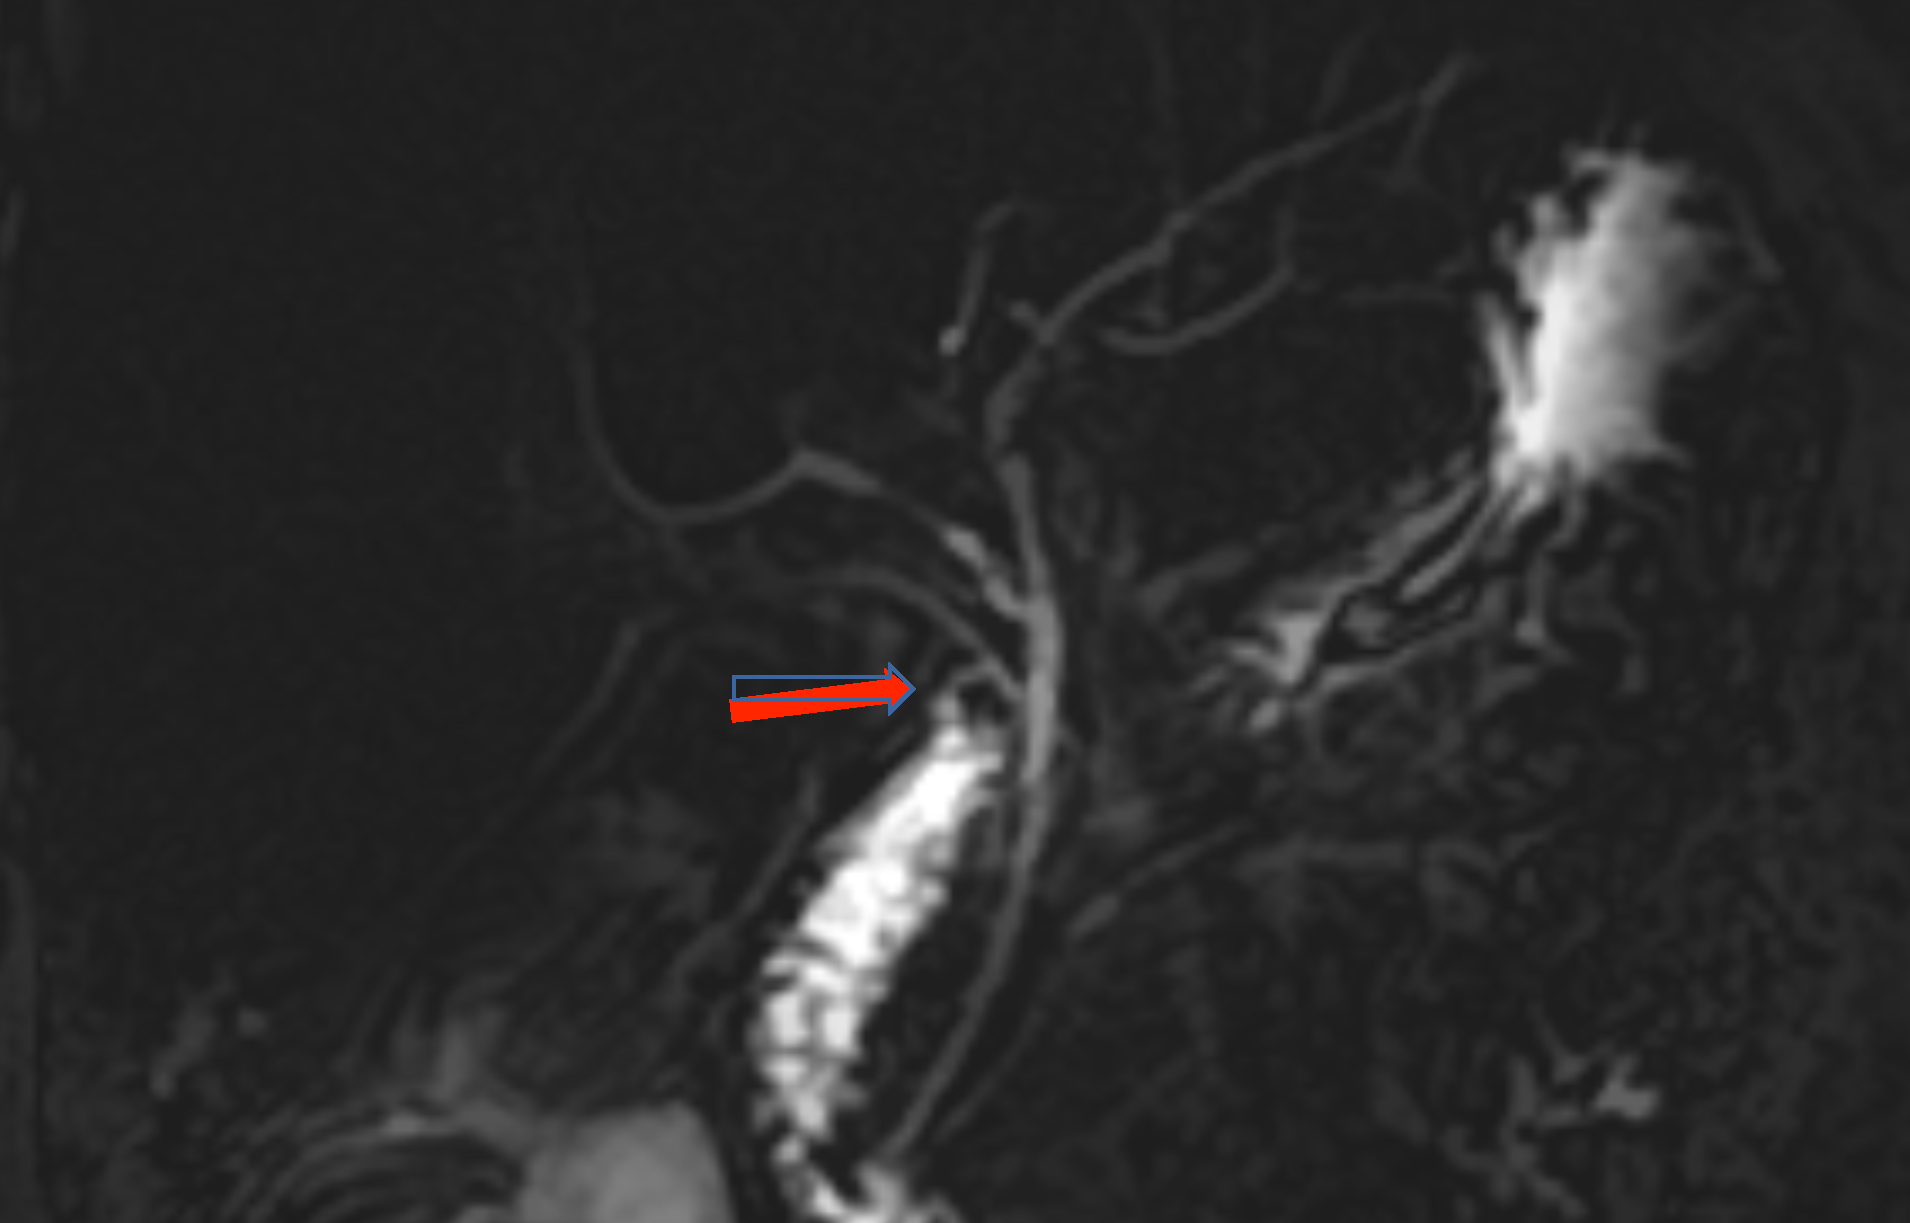

Magnetic Resonance Cholangiopancreatography (MRCP) was done, which showed leakage of bile from the common bile duct (CBD) (Figure 1). There was no bile leak from any other site. A plan for Endoscopic Retrograde Cholangiopancreatography (ERCP) was made, which also showed a side rent in the CBD, and biliary stenting was done. On the second day after ERCP, bile discharge occurred again from the wound. Repeat MRCP showed leakage of bile from a bile duct, which was running in the gallbladder fossa, draining into the common hepatic duct (Figure 2). After describing the situation to the patient and taking informed and written consent, a plan of exploration was made. On re-exploration through the Kocher’s right subcostal incision, three clips were found in the gallbladder fossa with a small collection. There was a leakage of bile from a minor opening in the bile duct running through the liver bed in the gallbladder fossa. This rent was closed with Polydioxanone 5/0 suture. Subhepatic drain was placed, and the abdomen was closed. The postoperative course of the patient remained uneventful with no biliary discharge in the drain, which was removed on the 4th postoperative day, and the patient was discharged in a haemodynamically stable condition.

Figure 1: MRCP showing bile leak from the common bile duct (red arrow).